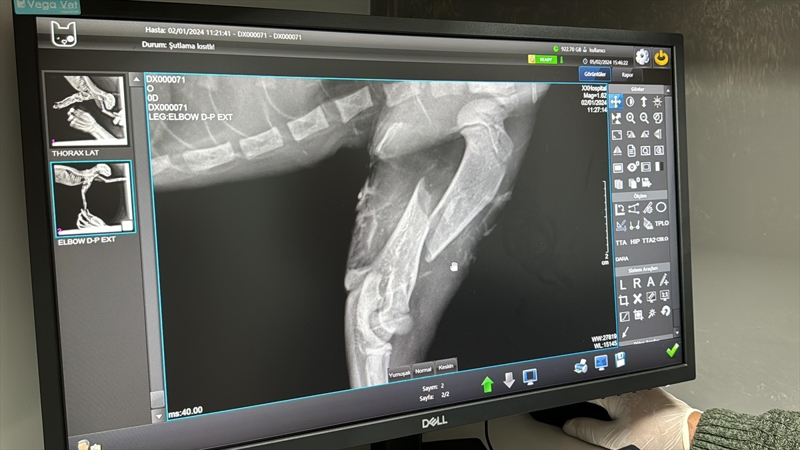

Karagöz, sağlıklı hayvanları kısırlaştırdıklarını da belirterek, "Donanım olarak çoğu hizmeti verebilecek durumdayız. Asıl amacımız kısırlaştırmak olmasına rağmen hasta hayvanların tedavilerini yapmaya çalışıyoruz. Bazen kırık vakalar, tümörlü hayvanlar oluyor. Bunları gayretle yapmaya çalışıyoruz." dedi.